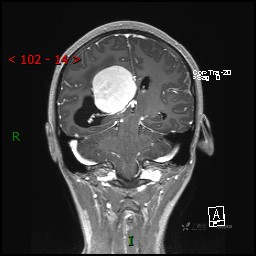

简要病史:患者于1月前无明显诱因出现视物模糊,无明显头痛头晕,无恶心呕吐,无昏迷,无肢体偏瘫等症状,就诊于当地医院头部CT考虑:右侧丘脑、脑室占位。予以对症处置后家属为求进一步诊治来我科,以“颅内占位”收入院。 起病以来,精神、饮食、睡眠欠佳,大小便正常,体力下降,体重无明显变化。

临床诊断:脑室占位

MRI平扫